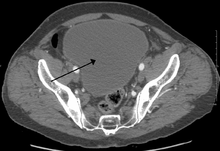

| Urinary retention with greatly enlarged bladder at CT. | |

Analysis of urine flow may aid in establishing the type of micturition (urination) abnormality. Common findings, determined by ultrasound of the bladder, include a slow rate of flow, intermittent flow, and a large amount of urine retained in the bladder after urination. A normal test result should be 20-25 mL/s peak flow rate. A post-void residual urine greater than 50 ml is a significant amount of urine and increases the potential for recurring urinary tract infections. In adults older than 60 years, 50-100 ml of residual urine may remain after each voiding because of the decreased contractility of the detrusor muscle. In chronic retention, ultrasound of the bladder may show massive increase in bladder capacity (normal capacity is 400-600 ml).